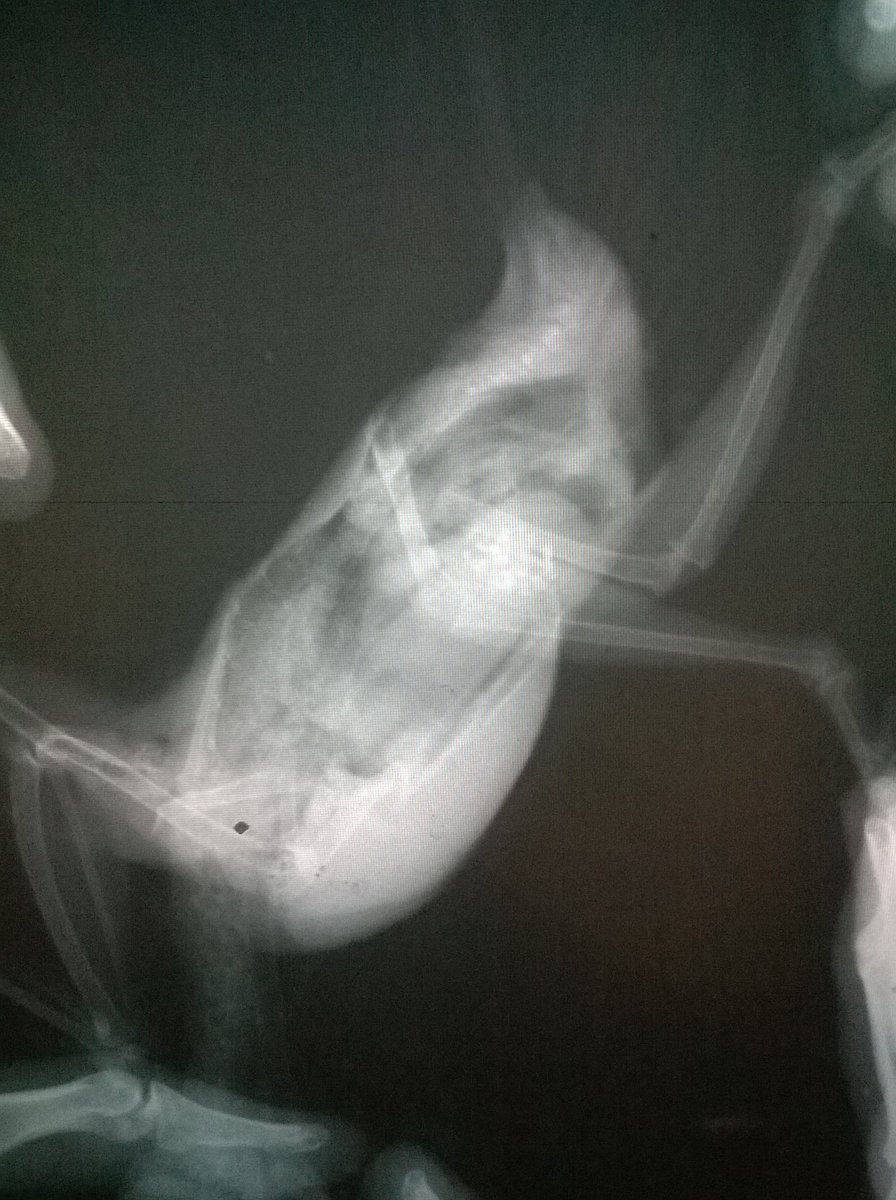

Возраст: 7 полных лет. Пол: женский. Порода: сизарь обыкновенный (Columba livia). Около 4-х месяцев назад голубка перестала нести яйца. Последние две пары снесенных яиц были значительно меньше обычных (не более 2 см.). Затем (в конце июля) появились странные выделения в помете (фото 1 и 2). Такие выделения начали выходить вместе с пометом примерно 1-2 раза в месяц. Когда у нее появляются эти странные выделения она ведет себя примерно так же, как во время кладки (хвост опущен, ищет место для кладки, разгребает, учащенно дышит). В остальное время голубка жизнерадостная и активная, ест и пьет хорошо, как обычно, летает, общается и т.д. Мы были у ветеринара, ей сделали рентген (фото 3 и 4). Доктор сказала, что у нее в брюшке эти сгустки - предположительно, остатки несформированного яйца. Эти сгустки могут накапливаться и давить на органы. Доктор предложила два способа решения: Инъекция (чего именно мы не знаем). При помощи этой инъекции, предположительно, голубка должна самостоятельно избавиться от этих сгустков, которые выйдут самостоятельно. Доктор сказала, что понаблюдает за ней в течение половины дня. Оперативное вмешательство. Если инъекция не подействует - доктор сказала что нужно будет делать операцию по очистке. Но при операции есть риск неудачного исхода. В общем от операции, над инъекцией думаем. Хотим собрать мнение еще нескольких специалистов, т.к. очень боимся возможного риска и не хотим сделать хуже. Пишу сюда, потому что хочу узнать мнения людей, встречавшихся с подобными ситуациями и так же мнения орнитологов и\или голубеводов, присутствующих на этом форуме. Заранее спасибо всем за ответ!- 3 ответа